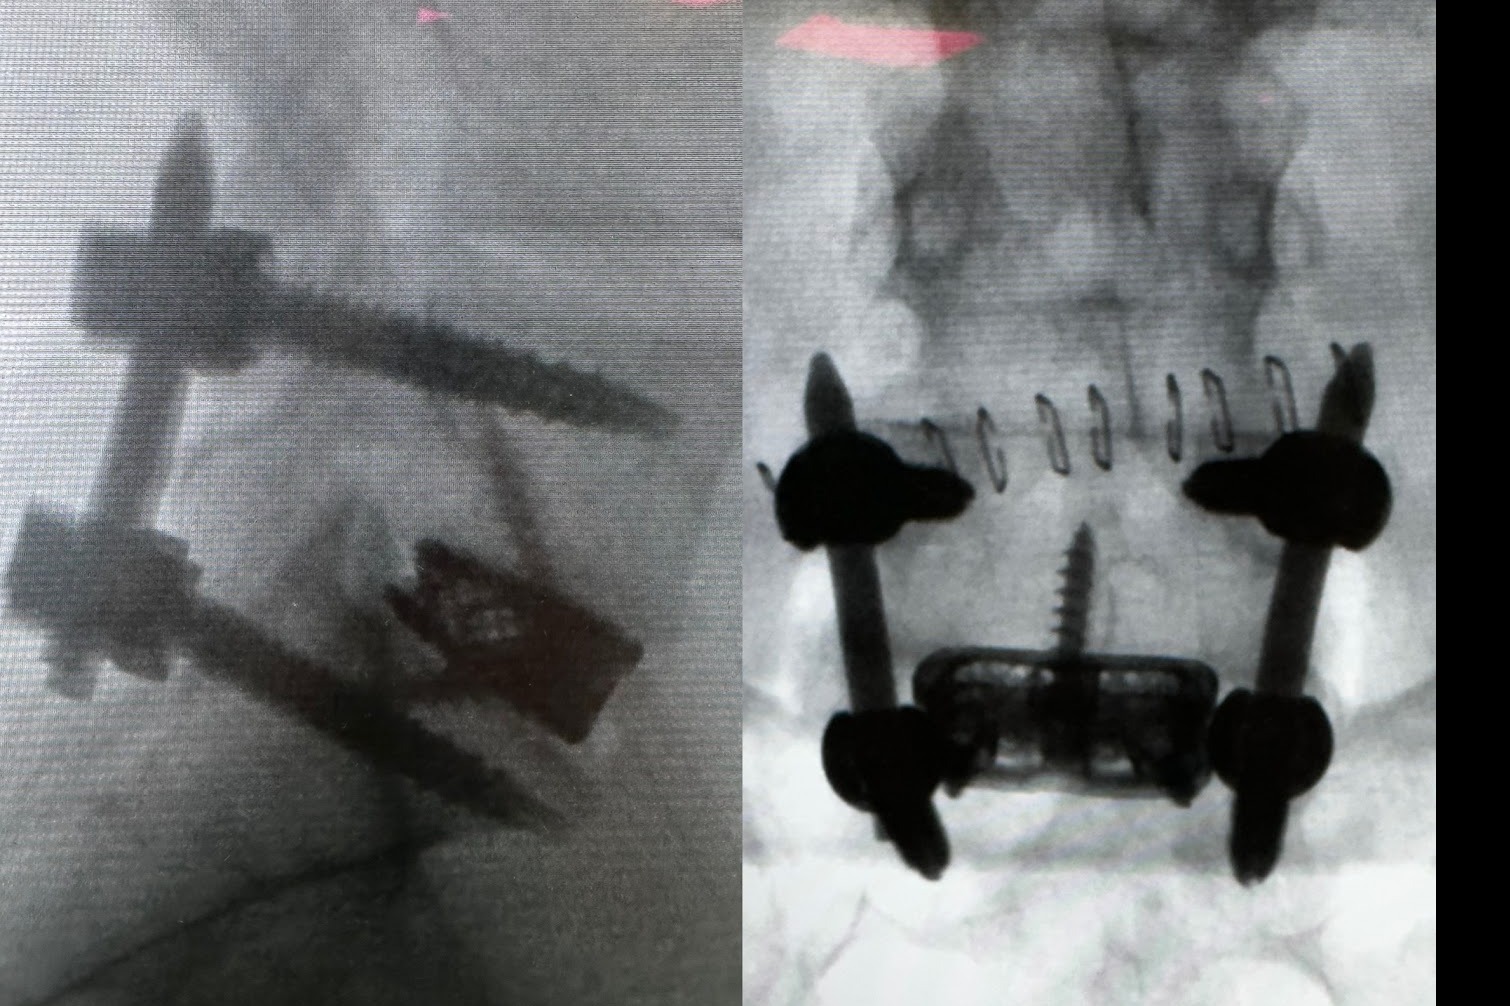

Ortopedia della Colonna Vertebrale